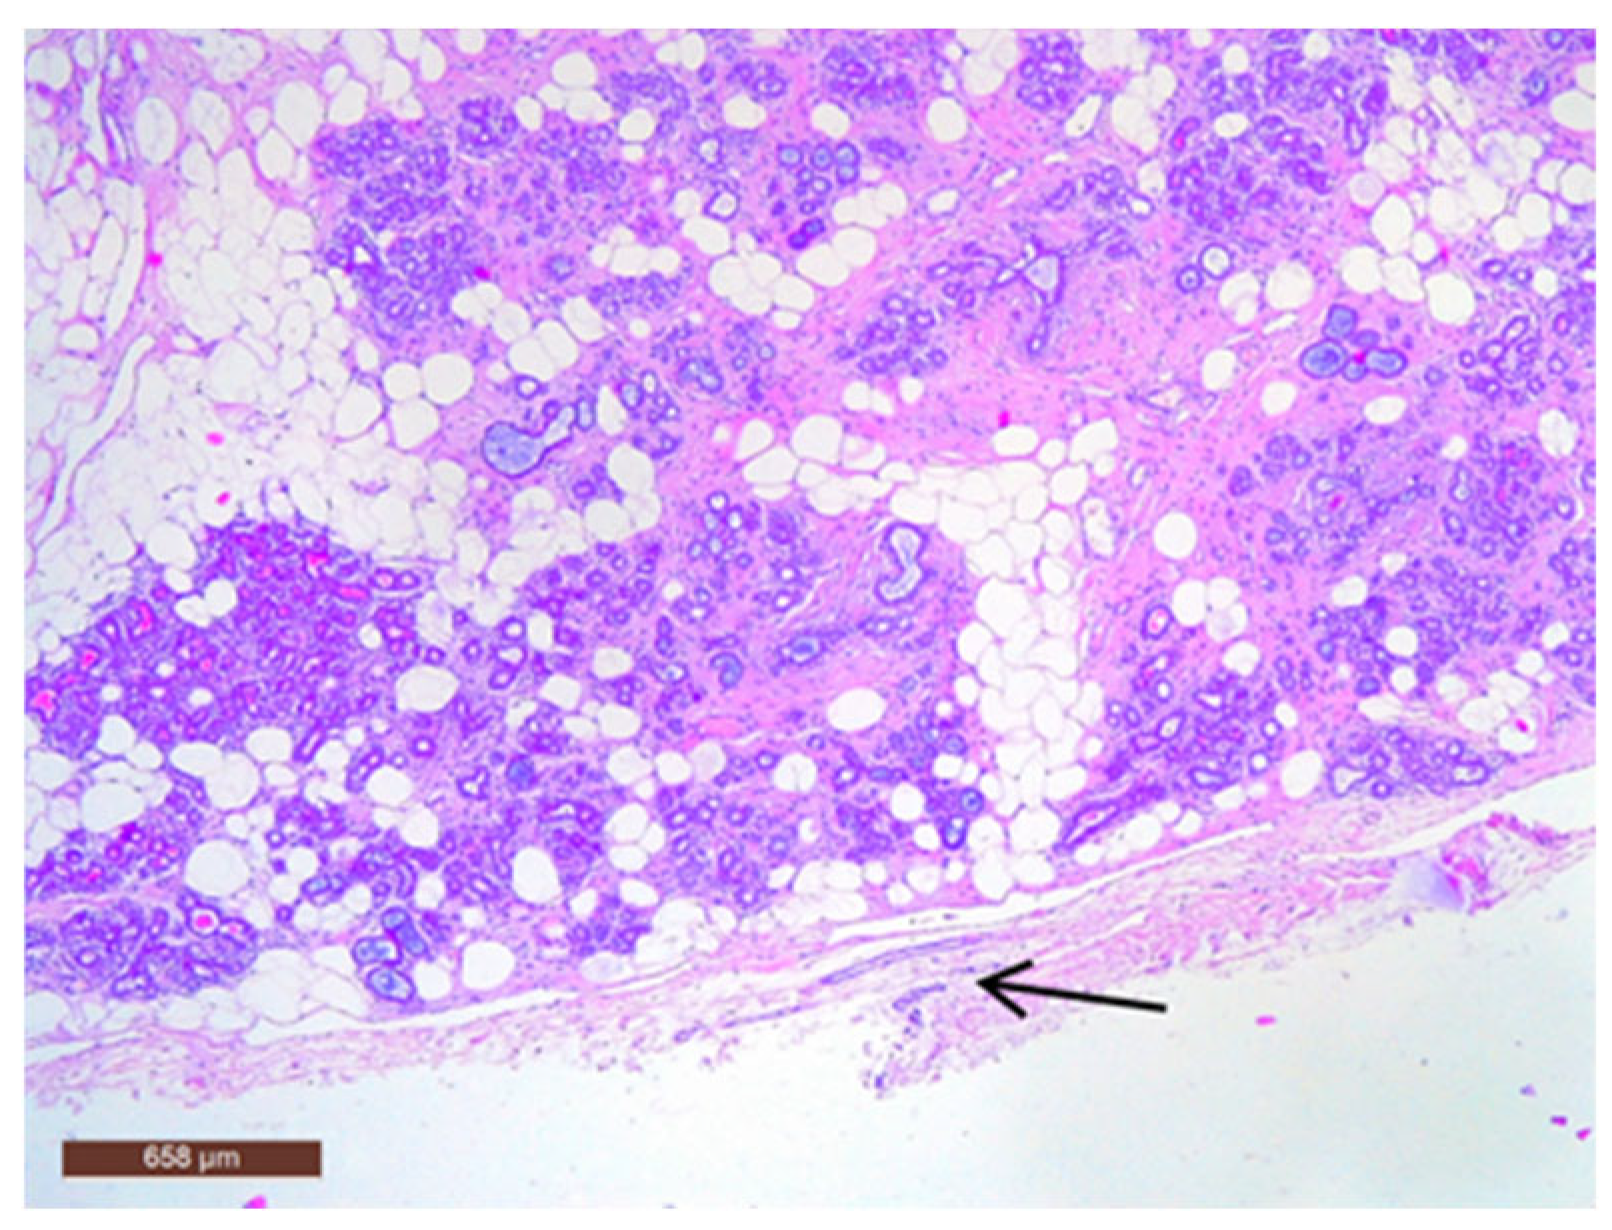

On microscopic examination, a hamartoma may exhibit three predominant components: glandular, fibrous and adipose (Figure 7). Epithelial components such as ducts and lobules are generally normal, featuring a single layer of epithelium overlying the myoepithelial cells. The fibrous component was composed of connective tissue stroma with a delicate connective tissue capsule (Figure 8). Additionally, the ducts within the hamartoma may display apocrine metaplasia (Figure 9).

Figure 7.

Hamartoma—histological structure (HE ×40).

Figure 8.

Hamartoma with fine connective tissue capsule (arrow) (HE ×40).